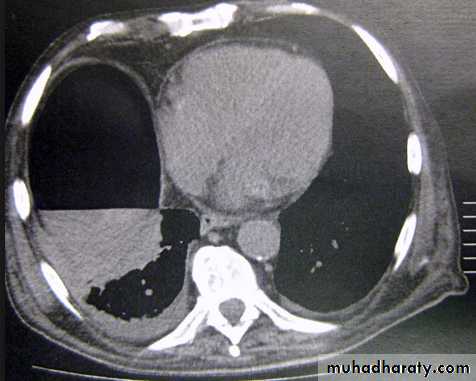

Pleural Effusion on Chest Radiographs.

Posteroanterior (A) and lateral (B) chest radiographs demonstrate the typical meniscoid appearance (arrows) in a patient with a left pleural effusion